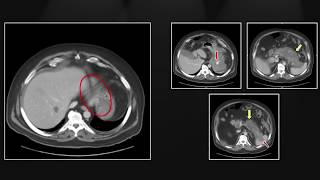

Pancreatic Emergencies | Interesting Radiology Cases

Pancreatic Emergencies | Interesting Radiology Cases Interactive CT Abdo Cases - Pancreatitis and Complications (Intro Level)

Interactive CT Abdo Cases - Pancreatitis and Complications (Intro Level) CT Normal Pancreas Vs Acute Pancreatitis | Balthazar Modified CT Severity Index (MCTSI) Scoring

CT Normal Pancreas Vs Acute Pancreatitis | Balthazar Modified CT Severity Index (MCTSI) Scoring Solid and cystic pancreatic lesion

Solid and cystic pancreatic lesion GI Imaging - Pancreatitis

GI Imaging - Pancreatitis Chronic pancreatitis with pseudocysts (Radiopaedia.org) Cases in Radiology

Chronic pancreatitis with pseudocysts (Radiopaedia.org) Cases in Radiology Grab Bag Emergencies | Interesting Radiology Cases

Grab Bag Emergencies | Interesting Radiology Cases Imaging in Pancreatitis

Imaging in Pancreatitis Acute Pancreatitis and Complications on CT

Acute Pancreatitis and Complications on CT